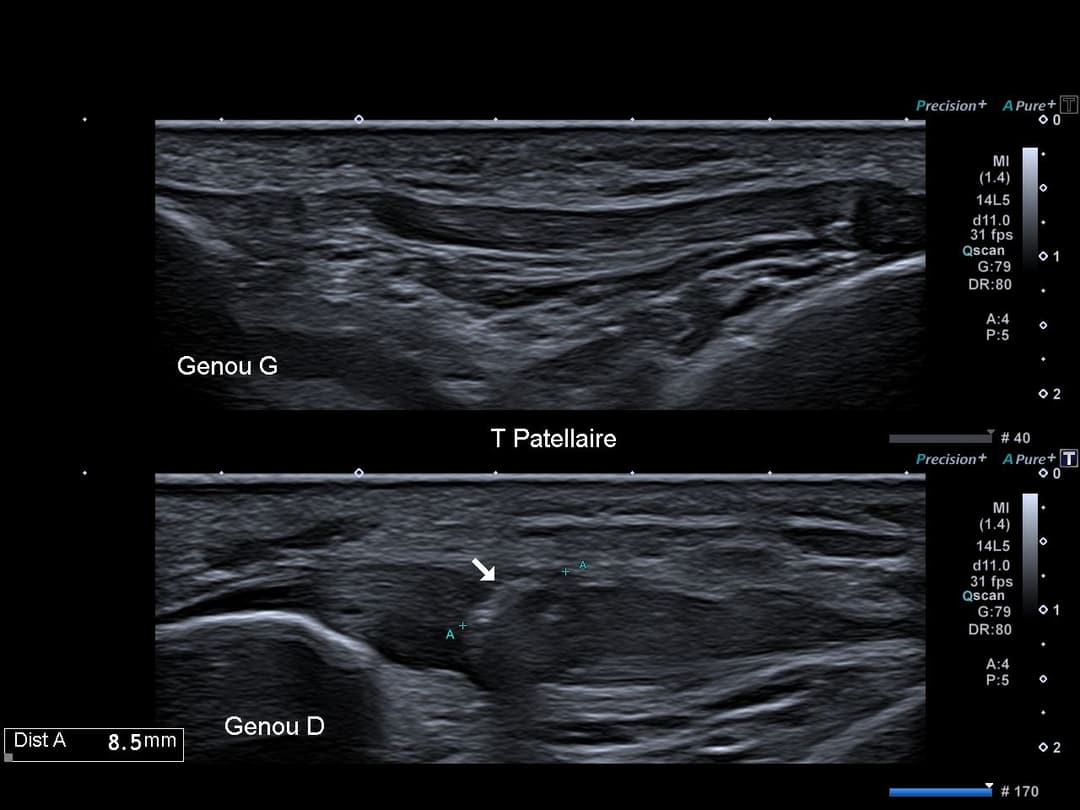

Calcification intra tendineuse corporéale ovoïde non atténuante de 8 mm.